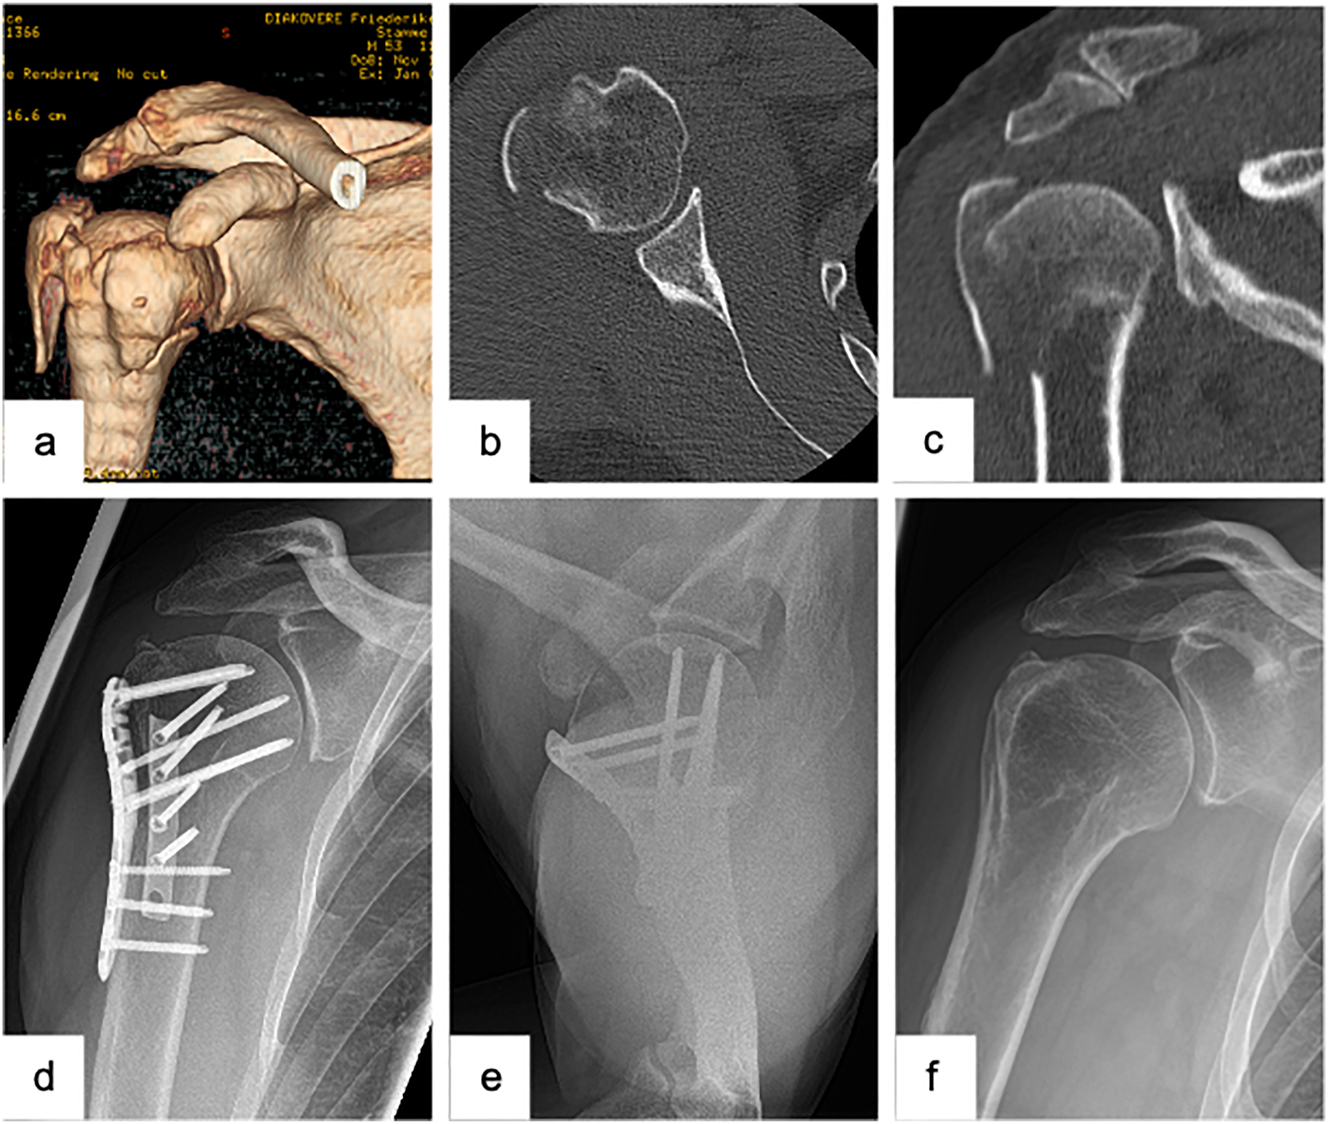

Dependent on the specific fracture morphology, the open reduction and Locking plate fixation (Figure 1) represents the main joint-preserving treatment option. Its aim is to achieve an anatomic reconstruction with a sufficiently medial support, thus leading to good functional results [15, 24], [25], [26].

Female patient (53 y), right shoulder, valgus impacted, dislocated 3-part proximal humerus fracture (preoperative X-ray and (3D-) CT-scan: a – a.p., b – 3D-CT-reconstruction, c – sagittal, d – coronal), open reduction and internal fixation with a locking plate osteosynthesis (postoperative X-ray: e – a.p., f – Y-plane).